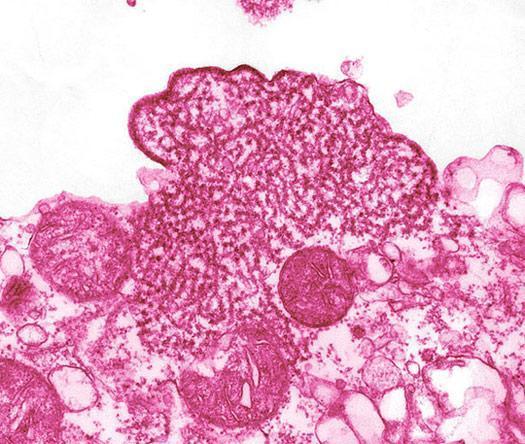

Nipah virüsü ateş, baş ağrısı, boğaz ağrısı ve kaslarda ağrı gibi belirtilerle kendini gösteriyor, gribe benziyor.

Ancak Nipah virüsü bulaşmış bazı insanlarda belirtiler hemen ortaya çıkmıyor.

İlerleyen safhada ise belirtiler baş dönmesi, yorgunluk, bilinç değişikliklerine dönüşebiliyor.

İlk defa Malezya'nın Nipah bölgesinde bir salgınla başlayan virüsün ayrıca biyolojik silah olduğuna dair iddialar da bulunuyor.

En çok Singapur, Malezya, Hindistan ve Bangladeş'te görülen virüs, meyve yarasaları aracılığıyla taşınıyor.